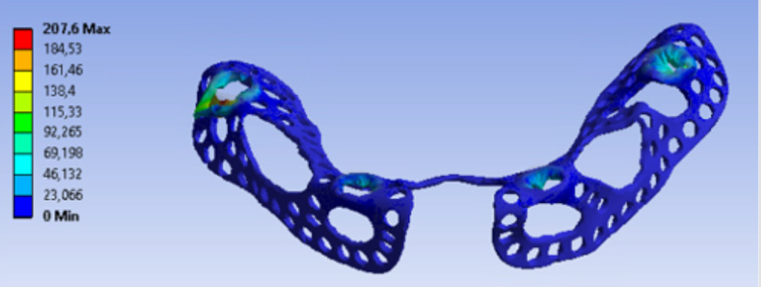

Distant forces were used as they would normally act on the implant from the dental crown. We used data obtained from scientific literature according to which magnitude occlusal forces can be between 100 and 800 N. In the first analysis, maximum 800 N occlusal force was defined. Its result is presented in Figure 7 It is notable that stresses only raised at the acting point of the force. Stress intensity was 287.28 MPa for maximum occlusal load. Another scenario was also investigated in which the frontal part of the implant was loaded with the lowest, while the back of the implant was loaded with the highest occlusal forces. Figure 8 presents the results of this loading scenario with the maximum stress level of 207.6 MPa. It is notable in this case that highest stresses raised at the back of the implant at the acting points of the forces. Different force variations were all analysed from minimum to maximum loads. Figure 9 shows the set of completely linear results. Highest stress intensity was 287.28 MPa for maximum occlusal forces. The studied implant was inserted after manufacturing. Implant fitting to the bone ridge of the patient can be seen in Figure 10.

In our mechanical analyses, the highest stress intensity was 278.28 MPa for maximum occlusal load. Yield strength of Grade 23 Ti-6Al-4V alloy is 760MPa, which means if we calculate maximum permissible stress with the safety factor of 2, the structure will still be safe. Volume reduction was successful. Consequently, the mass of implanted titanium alloy was reduced in the patient. Further studies will be conducted to further decrease the amount of titanium material.